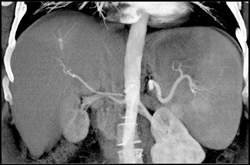

Hemangioma